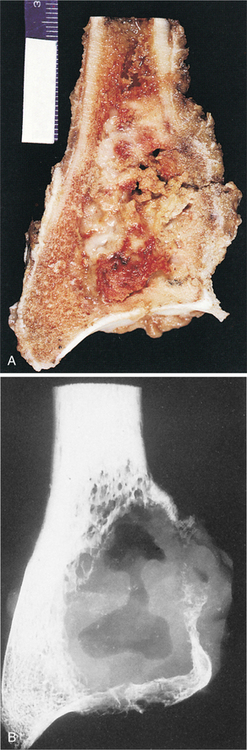

Pathologic examination of the neoplasm reveals a tumor that is soft, friable (easily breaks apart), fleshy, and red-brown with yellow areas. The tumor usually extends to but not into the articular cartilage. Destruction of the bone cortex with expansion into soft tissue can occur (Fig. 26-16). Hemorrhage, cyst formation, and necrosis can be seen on gross pathology. Hemorrhage and necrosis (often accompanied by pathologic fracture) occur often in the weight-bearing bones. The tumors can be locally invasive (into bone and soft tissue) with extensive bone destruction and cortical expansion.

Figure 26-16 Giant cell tumor. Gross morphologic features of giant cell tumor. A, Bisected distal end of radius with well-demarcated tumor mass expanding bone contour. Tumor tissue is red-brown with yellow septations. B, Radiographic presentation of tumor showing focal destruction of cortex. (From Dorfman HD, Czerniak B: Bone tumors, St Louis, 1998, Mosby.)